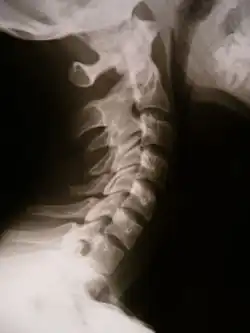

|  X-ray showing synostosis in the cervical spine | |

Synostosis (plural: synostoses) is fusion of two or more bones. It can be normal in puberty, fusion of the epiphyseal plate to become the epiphyseal line, or abnormal. When synostosis is abnormal it is a type of dysostosis. Examples of synostoses include: